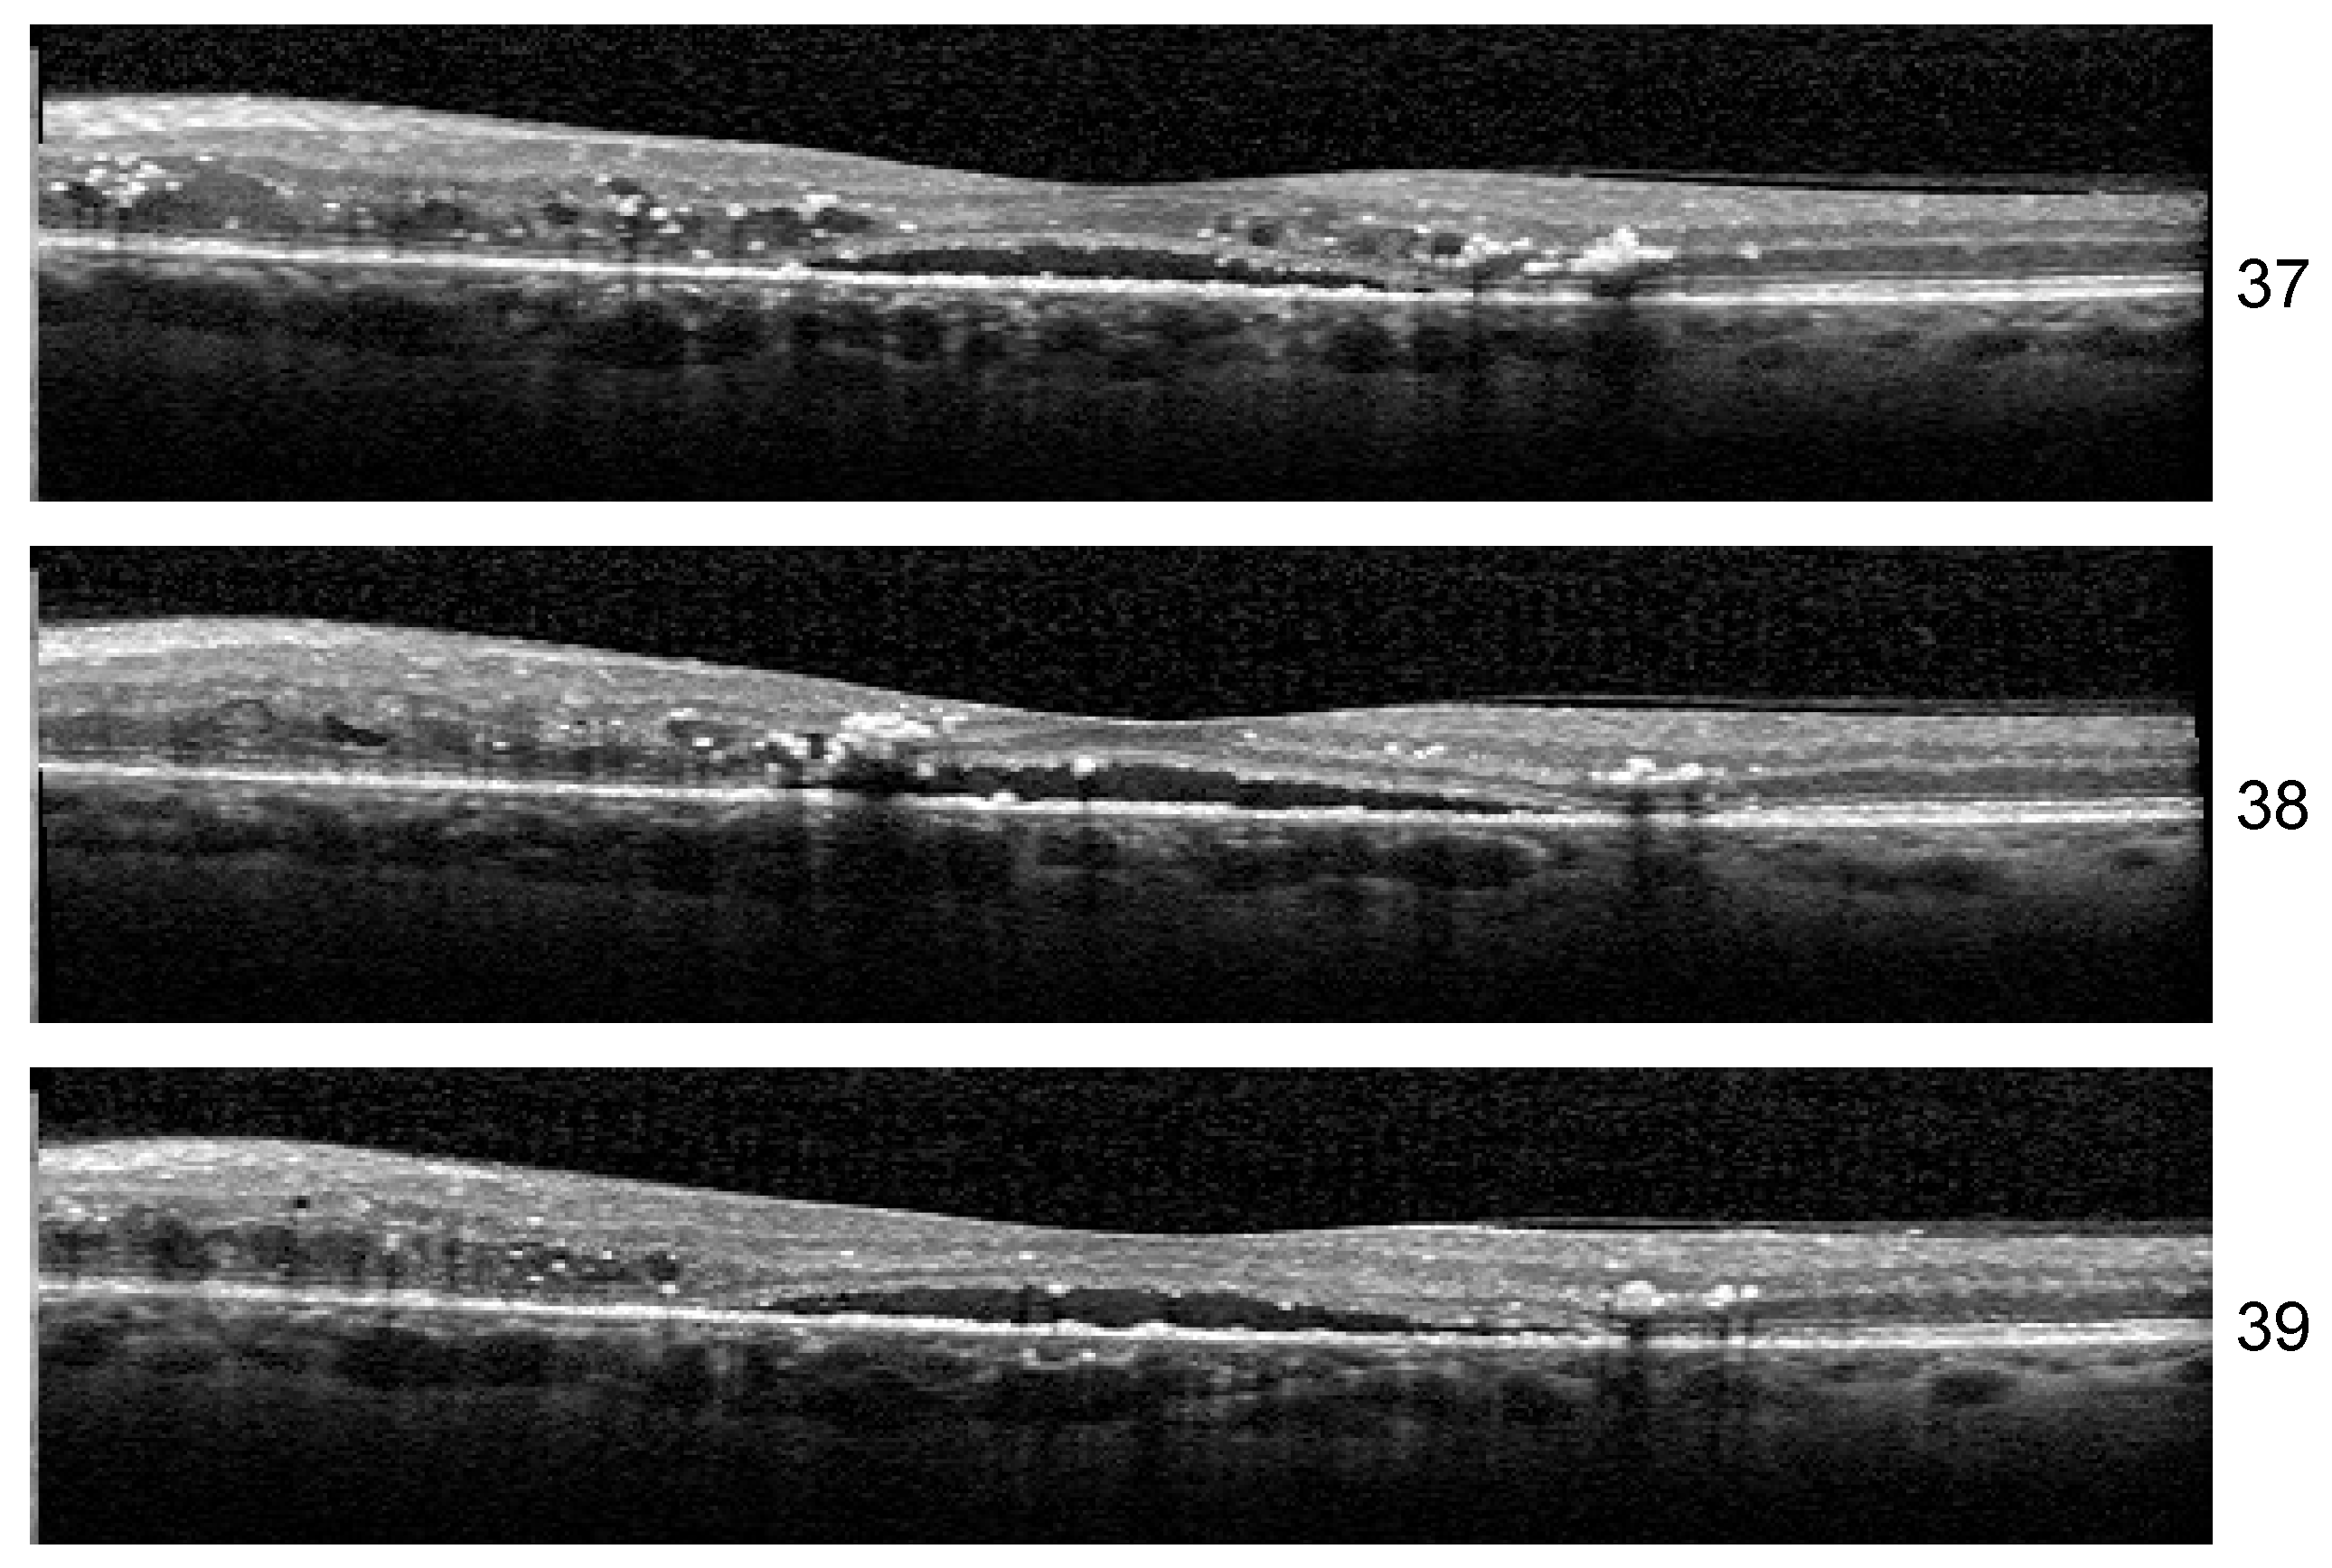

Stability: Unlike the results of Experiment 1, the misclassified examples change within different architectures or even the same architecture but different training. If Set 1 is consistently misclassified by all the runs of the Experiment 1 with one exception, in the case of three biomarkers, the errors in the identification of less obvious biomarkers varies along different runs. One such example is the HF scan from patient B02 left eye, slice 39, illustrated in Figure 13. The model for which we report the performance and Grad-Cam visualization identified it as healthy, but the same architecture, with a minor change in training, predicts that the image is not healthy but also that none of the biomarkers (DME, HF, or ND) is present.

Figure 13.

DME+HF+ND scans inside a sequence.

Another curious behavior was observed for scan 38 from the sequence in Figure 13. There were runs from all the architectures that could correctly predict for all three scans the presence of all three biomarkers, but in more than one run, scan 38 was predicted only to have DME and HF while both neighboring scans were predicted as DME+HF+ND. The reason behind this is not yet clear, but we suspect that the presence of HF exactly near the detachment impairs the model’s ability to consider the presence of ND.

Even though the lack of complete stability indicated limitations in our study, which are mainly related to the size of the dataset, the large values for Seq IoU indicate that the “three biomarker” model is able to detect the presence of DME, ND, or HF in a volume, while potentially missing their presence in some B-scans from the volume.